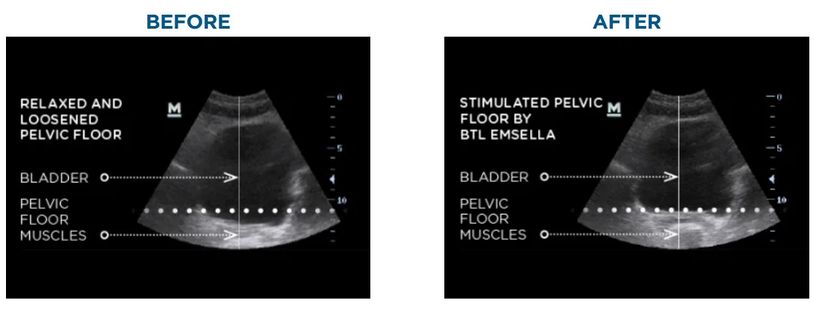

Emsella is an FDA-cleared device that uses High-Intensity Focused Electromagnetic (HIFEM) energy to stimulate deep pelvic floor muscle contractions—similar to performing over 11,000 Kegels in a single session. This powerful technology helps retrain and strengthen pelvic floor muscles, improving bladder control and enhancing overall intimate health and quality of life.

You’ll simply sit on the Emsella chair—fully clothed—while the device delivers electromagnetic pulses that target the entire pelvic floor. You’ll feel a series of tingling and deep contractions, but no pain. Most patients see results after just a few sessions, with optimal benefits after a series of six.